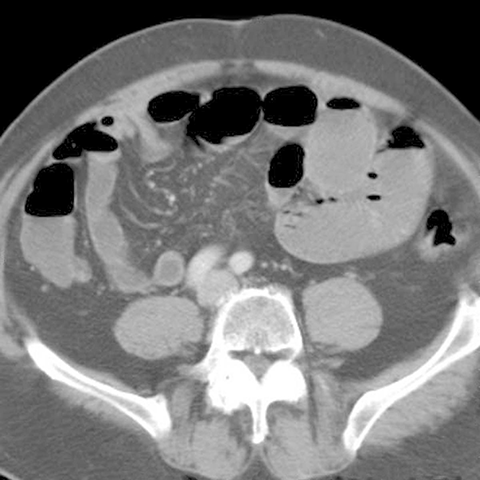

Small Intestinal Obstruction, axial CT [3 of 3]